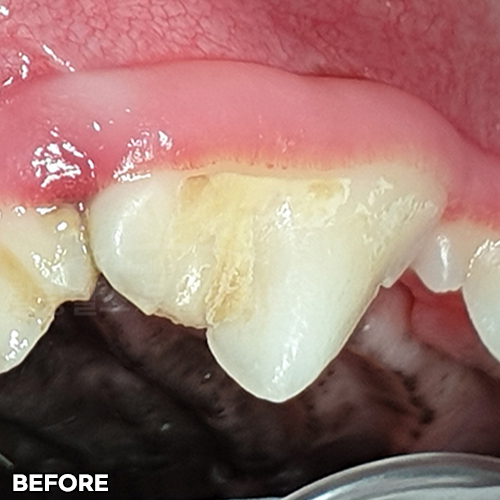

[구멍난 강아지 치아 레진치료 전후]